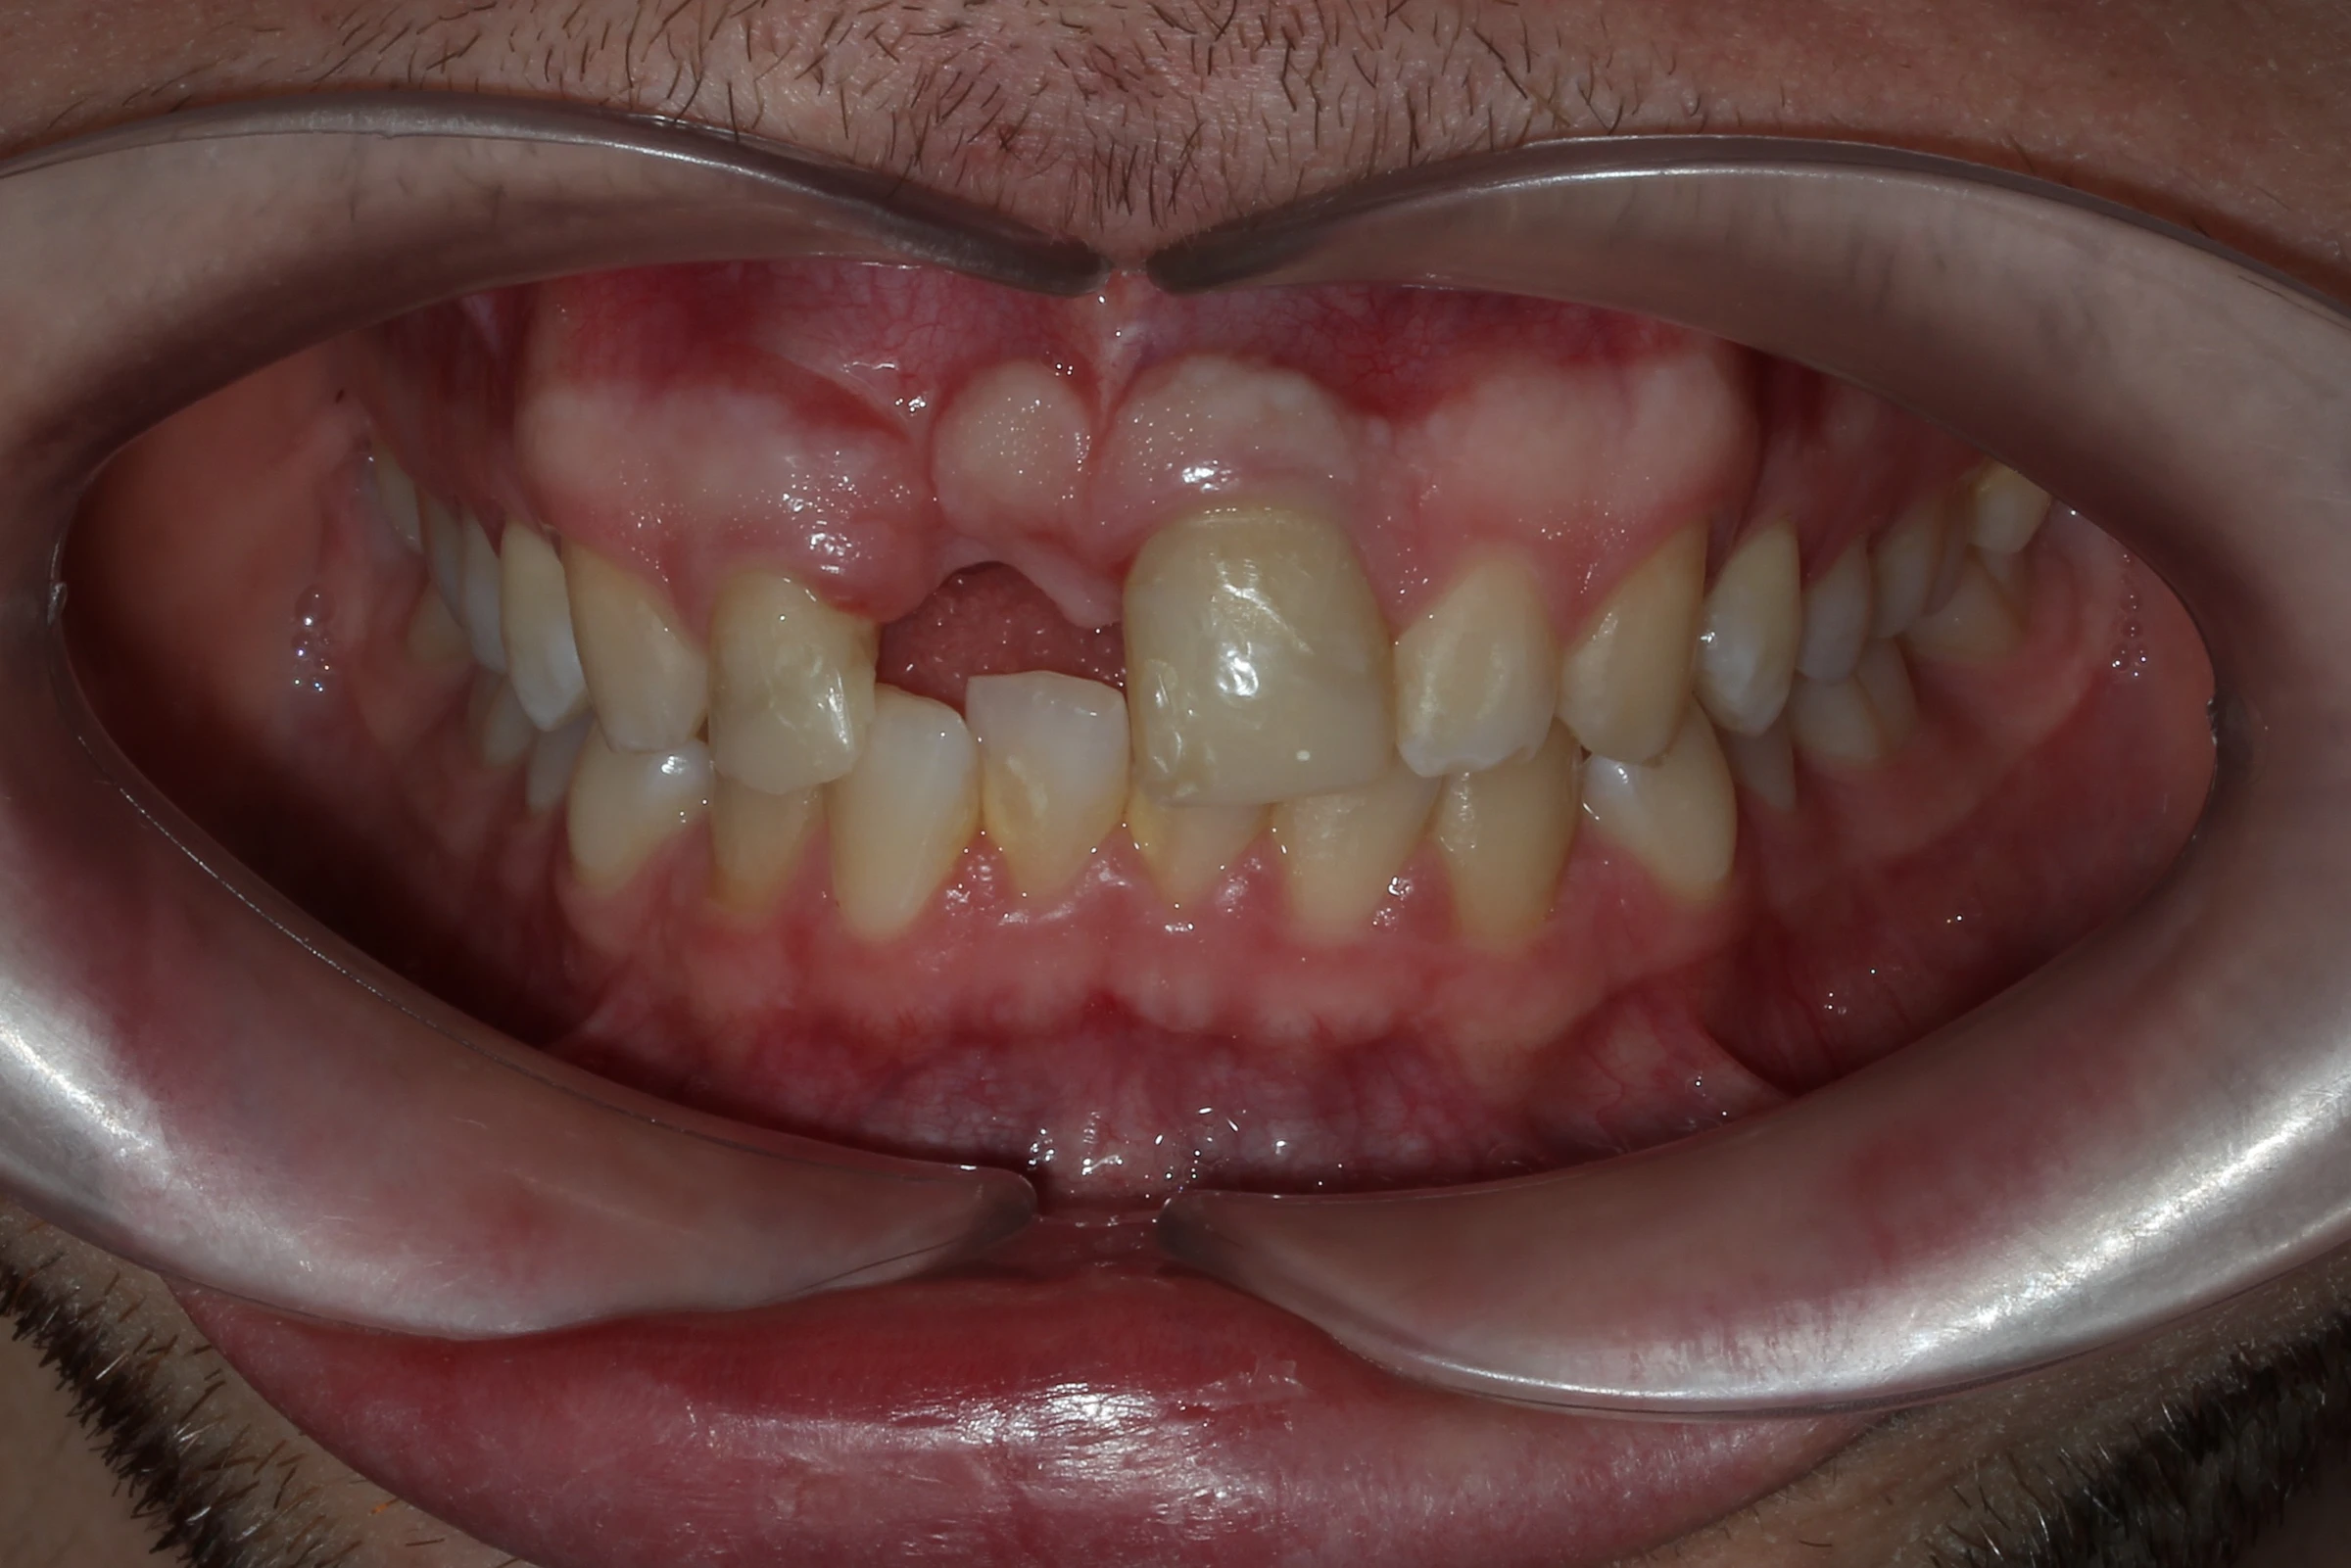

Diagnosticul inițial

Pierderea incisivului frontal

Traumatism dentar cu avulsia completă a dintelui 21

Defect osos alveolar

Resorbție osoasă moderată în zona edentată

Impact estetic și funcțional

Dificultăți fonetice și disconfort estetic marcat

Alexei, un tânăr energic și activ, a suferit un accident în timpul unei vacanțe cu prietenii, în urma căruia a pierdut un incisiv superior central. Pe lângă impactul estetic major, trauma a dus și la pierdere de volum osos și gingival în zona afectată, ceea ce a făcut necesară o reabilitare implanto-protetică complexă.